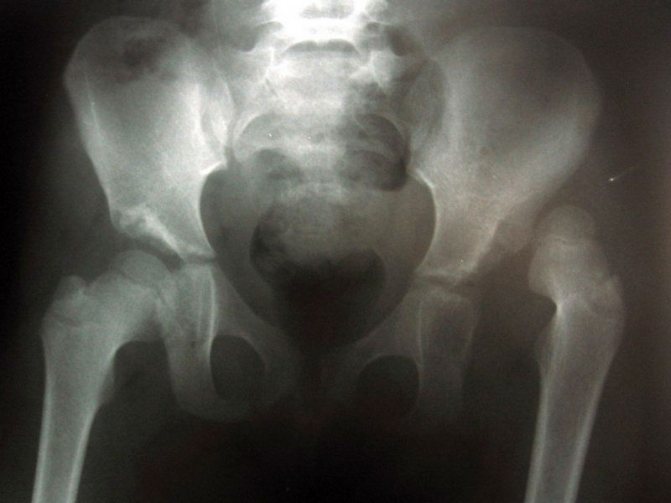

- Рентген можно делать крохе после 1 года. Конечно, при необходимости врачи могут назначить подобное исследование и раньше, но до 7 месяцев на снимке различить состояние суставов будет сложно, так как они еще недостаточно окостенели.

Диагностировать наличие ДТС может специалист, проведя визуальный осмотр ребенка, анализируя рентгеновский снимок и результат УЗ исследования. Поскольку начальные стадии развития патологии визуально определить затруднительно, при малейшем подозрении на наличие проблемы рекомендуется посетить ортопеда.

Для его подтверждения назначаются инструментальные исследования, обычно ультрасонография (УЗИ ТБС). Используется в диагностике и рентгенография, но только у детей старшего возраста. Дело в том, что до 3 месяцев в тазобедренном суставе еще много хрящевых тканей, которые не просматриваются на рентгенографических изображениях.